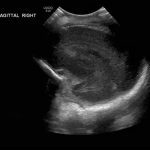

Age: 4 days (born at 24 weeks)

Sex: Male

Indication: Evaluate for germinal matrix hemorrhage

Grade 2 germinal matrix hemorrhage

Sample ReportLeft germinal matrix hemorrhage involving the caudothalamic groove and layering in the occipital horn of the left lateral ventricle without hydrocephalus (grade 2).

No abnormal brain parenchymal echogenicity or extra-axial collections.

Premature sulcation pattern.